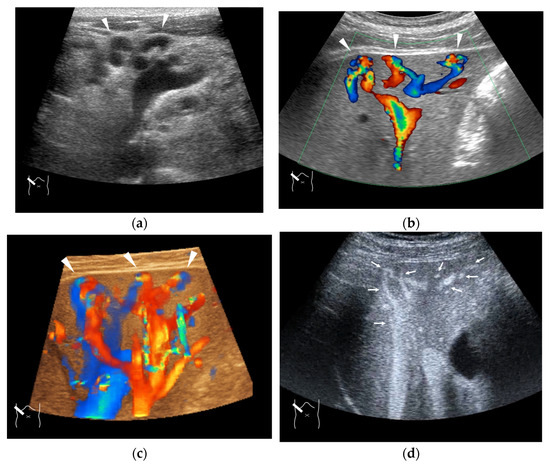

4.6. Hemodynamic Abnormalities in Acute Cholecystitis

5. Future Perspectives

6. Conclusions